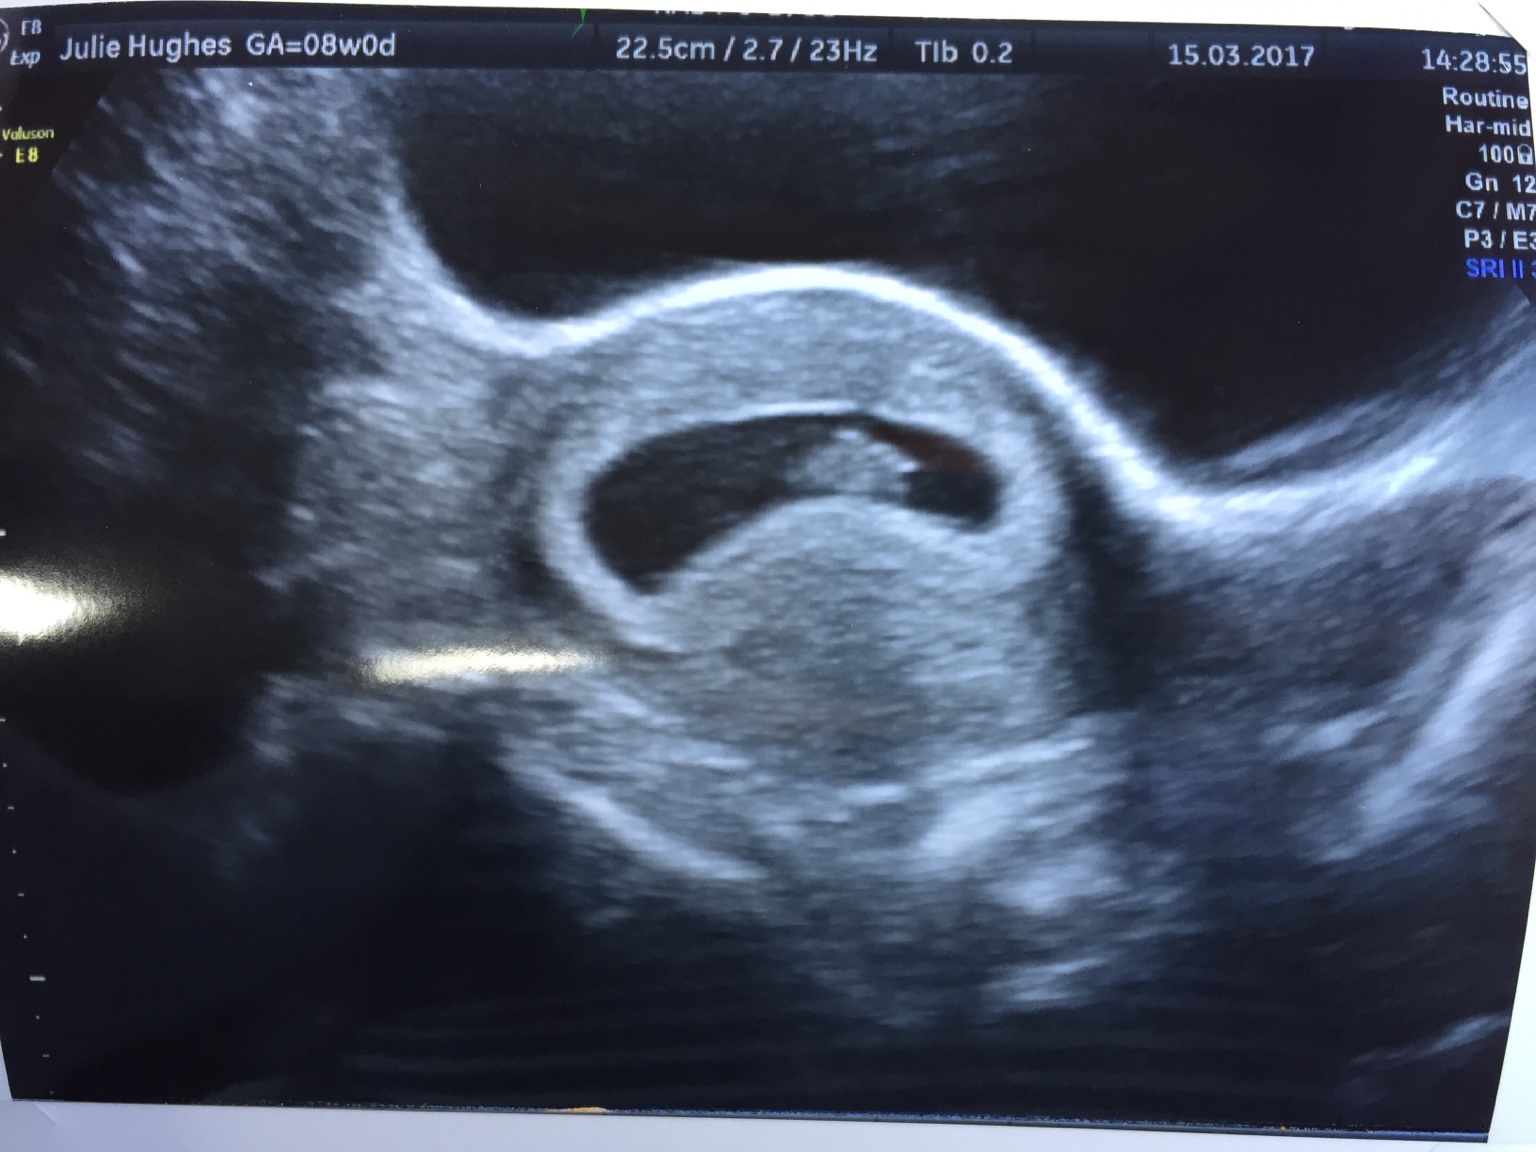

If you're pregnant in England you'll be offered an ultrasound scan at around 10 to 14 weeks of pregnancy . This is called the dating scan . It's used to see how far along in your pregnancy you are and check your baby's development . The scan may also be part of a screening test for Down's syndrome .

When will I have my dating scan ? You'll have a dating scan appointment, also known as a 12-week scan , between about 10 weeks and 14 weeks of pregnancy . This is usually the first scan you'll have, so it's likely to be a significant moment for you . You'll only have a scan before 10 weeks in certain situations . For example, if you had assisted conception, an early scan will check the embryo is developing as it should .

When will I have my dating scan ? Your dating scan is usually offered between about 10 weeks and 14 weeks . For most women, the dating scan is their first scan . During the scan , the sonographer will put gel on your tummy and move the transducer over your skin .

When will I have my dating scan ? The dating scan is an ultrasound that can be done from seven weeks of pregnancy but they usually happen a little later . It's the best way to predict your due date (Butt and Lim 2014, PHE 2014, SOGC 2019, Van den Hof et al 2019) . It's also a chance for you to see your baby for the first time . Not all moms-to-be have a dating scan .

A dating scan might be recommended before 12 weeks to confirm your due date if you are unsure of your last menstrual period or your date of conception . The scan is optional and not everyone will have it . You can discuss whether you want or need a dating scan with your doctor or midwife . A dating scan is usually done to check how many weeks' pregnant you are, but can be done for other reasons, such as if you have had bleeding during your pregnancy or you have had previous miscarriages .

I am 7 weeks pregnant with my first baby, my GP sent me for a scan at when we predicted I would be 6 weeks for a dating scan . When I went to the ultrasonographer, she said that I was 5 weeks 4 days . At this time she did an external and internal ultrasound . DH and I could see a heart beat on the screen .